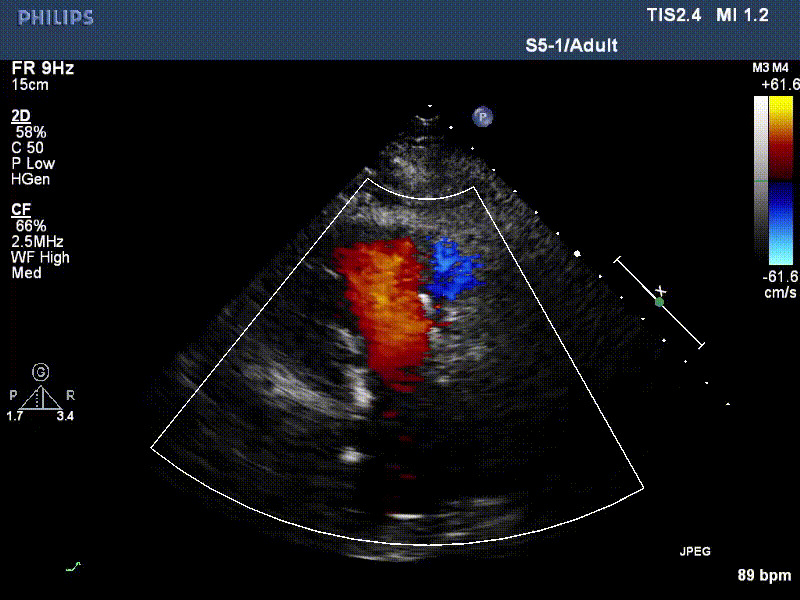

流并分別伴有房顫和房撲,高外科手術(shù)風(fēng)險。術(shù)前超聲提示,兩例患者下腔靜脈寬度分別為13mm和29mm,右房內(nèi)徑(上下徑和左右徑)分別為52×41mm和53×43mm,彩色多普勒顯示極重度三尖瓣反流,VCW分別為14×15mm和10mm。

1年前,兩例患者因難治性雙下肢水腫輾轉(zhuǎn)多家醫(yī)院尋求救治,考慮到兩例患者高齡、基礎(chǔ)疾病多、STS評分高,不適合傳統(tǒng)外科開胸手術(shù),葛均波院士及其團隊周達新教授、潘文志教授、張源博士、陳莎莎博士、陳丹丹博士聯(lián)合心外科王春生、魏來主任,麻醉科繆長虹、郭克芳主任以及心超室的潘翠珍教授、李偉教授共同討論決定,采用我國創(chuàng)新器械LuX-Valve Plus經(jīng)血管三尖瓣置換系統(tǒng)為患者進行手術(shù)。相較于第一代產(chǎn)品LuX-Valve,LuX-Valve Plus經(jīng)血管三尖瓣置換系統(tǒng)對輸送系統(tǒng)進行了全面升級,實現(xiàn)了經(jīng)頸靜脈入路的方式,進一步減小了手術(shù)風(fēng)險和對患者的創(chuàng)傷。目前隨訪1年心超結(jié)果顯示,三尖瓣極重度反流消失,人工三尖瓣瓣膜穩(wěn)定牢固,瓣葉活動度良好,右心室及下腔靜脈明顯縮小,心輸出量增加。兩位老人手術(shù)后沒有出現(xiàn)過胸悶氣促的癥狀,下肢水腫緩解,活動耐力提升,生活質(zhì)量也大為提高。

圖2 患者植入LuX-Valve Plus后,1年隨訪心超提示無三尖瓣反流